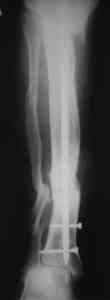

Вложение не в текстовом формате было извлечено…

Имя     : 6.jpg

Тип     : image/jpeg

Размер  : 32638 байтов

Описание: отсутствует

Url     : http://weborto.net:8080/pipermail/ortho/attachments/20080516/529c86f2/attachment-0007.jpg